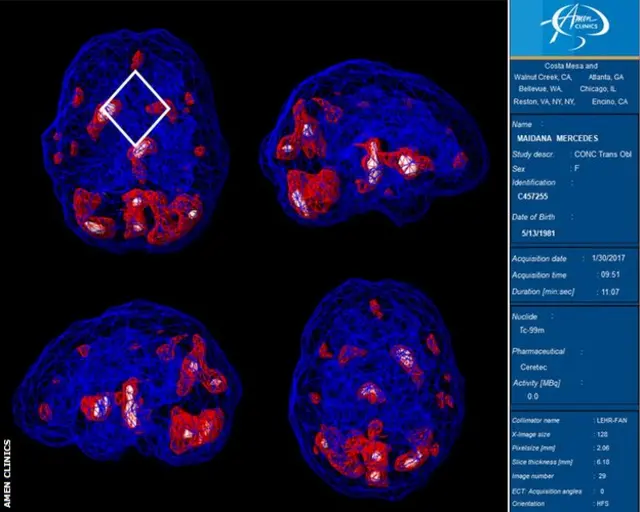

„Završila sam na jednoj kalifornijskoj klinici, gde su uradili SPECT [jednofotonska emisiona kompjuterizovana tomografija] skeniranje kako bi videli šta se zaista dešava u mom mozgu - koji su delovi bili aktivni, a koji uspavani", kaže ona.

„Moj mozak je uglavnom bio zaceljen, ali patila sam od teškog posttraumatskog stresnog poremećaja. Plan oporavka se preusmerio na emocionalno zdravlje i u tom trenutku se moja dijeta u potpunosti promenila.

„Batalila sam šećer, mlečne proizvode, svu procesuiranu hranu i alkohol. Morala sam veoma zdravo da se hranim. Dali su mi suplemente koji poboljšavaju funkciju mozga, kao što su riblje ulje i razni vitamini, i terapiju koja će se usredsrediti na moje emocije. Dali su mi odgovarajuće antidepresive. Ubrzo posle toga počela sam da se oporavljam."